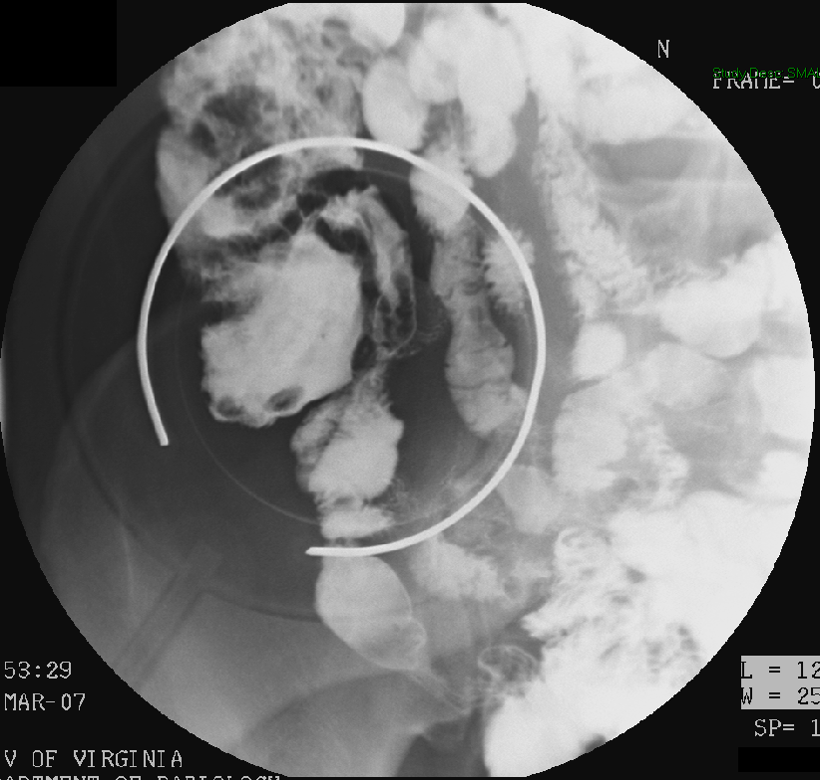

- Slide a compression paddle under the patient (balloon deflated) so that it is positioned on the duodenal bulb.

- There is a radiopaque ring on the paddle that will help you determine the center of the paddle.

- Inflate the bulb on the compression paddle and obtain single contrast compression spot films of the duodenal bulb and the C loop

(key image 14)

(key image 15)

(key image 16)

(key image 17)

(key image 18).

- Once the table is horizontal, obtain spot images of an air filled duodenal bulb. Placing the patient in a slightly steep left posterior oblique is usually best for obtaining these images.

(key image 22)

(key image 23)

(key image 24)

(key image 25)